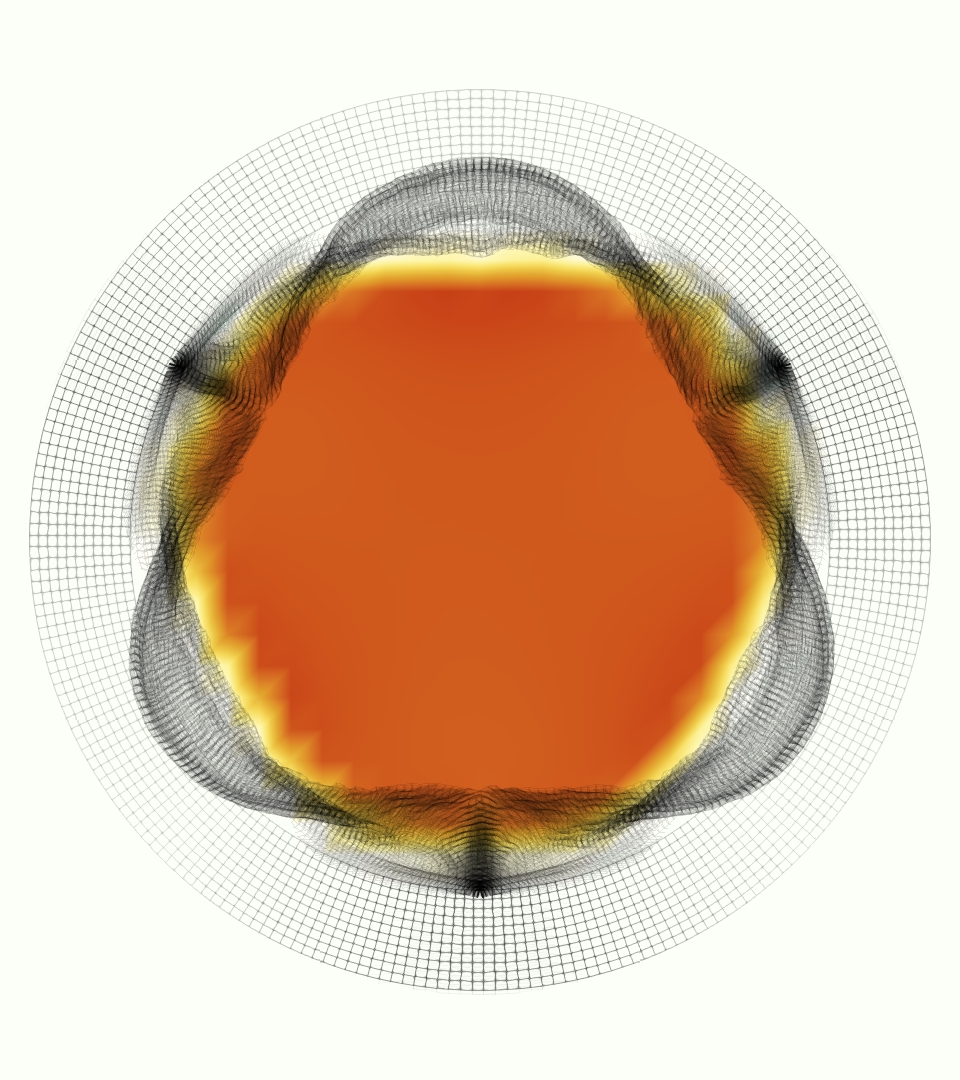

The gross morphology of the model valve that emerged from this process is shown in Figure 4. The free edge was 2.87 cm, corresponding to 3.3 cm in the predicted loaded configuration. After the pinching the leaflets together at the commissures, this left approximately 2.1 cm of free edge rest length per leaflet free to move independently of the other leaflets, within measurement error of ±0.1 cm from the free edge length of 2.2 cm measured on the prostheses. The leaflet rest height was 0.94 cm corresponding to a predicted loaded height of 1.44 cm. The measured leaflet height of 1.3 cm is nearly the predicted loaded height of 1.44 cm, which may be because the leaflets are so compliant in the radial direction, that pulling them flat to measure them achieved substantial stretches. The fiber orientation of the model runs from commissure to commissure and qualitatively matches experimental observations [38], though direct quantitative comparison is beyond the scope of this work. One minor limitation is that we do not add bending rigidity to the leaflets, beyond what emerges from the thickening process described above, and thus may not accurately capture leaflet flutter or other similar behaviors. Based on the thickness of mm, we estimated the mean tangent modulus at the predicted loaded stretches as dynes/cm2 circumferentially and dynes/cm2 radially. The prosthetic valve tissue is fixed in glutaraldehyde, and literature values for the fully-recruited circumferential tangent modulus of fixed porcine aortic valve tissue vary widely. Based on the experimental measurements of Billiar and Sacks and their constitutive law for valves fixed under 4 mmHg of pressure, we evaluated their constitutive law at the relevant stretches and and estimated the circumferential tangent modulus to be dynes/cm2 [6]. Rousseau et al. reported moduli ranging from to dynes/cm2, depending on the applied preload during fixation [36]. Sung et al. reported moduli ranging from to dynes/cm2, depending on fixation pressure [43]. Thus our estimated tangent modulus falls within the range of existing studies, so we considered our resultant modulus in good agreement given the complexity of the steps involved, phenomenological nature of the constitutive law and uncertainties in experiments. We do not have access to the precise material properties of the prosthetic valve, and further, the only literature we could find on the material properties of a similar prostheses reported the tangent modulus at one particular loading, which did not appear to be at a relevant stretch for comparisons with our model [19]. Thus, our model has material properties in a reasonable range for a fixed aortic valve prostheses (placed in the pulmonary position in our simulations), but it does not directly model the material properties of the prostheses.

We constructed the model vessel for FSI simulations from data from the MRI scans (Figure 4). The signal magnitude of 3D printed model material is distinct from the signal of the fluid in the scans, and we applied a thresholding operation to generate a three-dimensional model of the printed vessel surface. Using the MRI data ensured that the MRI and simulation coordinates were consistent in space and there were no alignment or registration errors. While using the files that generated the 3D printed model would have offered more spatial fidelity, the potential error in flow fields due to any mis-registration would have likely been much more substantial. Using Meshmixer (San Rafael, CA), we smoothed the mesh to remove stair-step effects and removed artifacts from the valve scaffold. We then remeshed to the desired edge length of 0.25 mm and extruded the model 0.25 mm and 0.5 mm to create a three-layer structure. As in the valve, this serves to eliminate the “grid aligned artifact” that can occur with pressure differences across thin membranes in the IB method [16]. Flow extenders of length 1 cm were added to the vessel at the inlet and both outlets to ensure that the normal to the vessel was aligned with the normal of the fluid box at the inlets and outlets. In FSI simulations, the vessel was held in place using target points, stiff springs of zero rest length that connect the current position of each model node to its desired position (Section 3.3). Additional linear springs are placed on each edge in the triangulated model. These springs are not meant to model a particular material and only serve to keep the vessel rigid and stationary throughout the simulation.

At = 0, the axial slice directly at the valve annulus shown in columns 1 and 2 in Figure 6, there was excellent agreement between the simulation and experiment over the cardiac cycle in the speed and shape of the jet through the valve. In both cases, the axial velocity increased as the flow accelerated during systole and the valve leaflets opened, then decreased during diastole with slight negative velocity before the valve leaflets were fully closed. The forward flow through the valve annulus did not form a full circle, but rather developed a triangular shape with a point of the triangle forming along the interior curve of the vessel, at the bottom of the axial slices. At = 0, the points of this triangular jet shape aligned with the commissures of the valve. This shape persisted during peak systole and was well-matched by the simulation.

The axial slice = 0.625 cm, shown in columns 3 and 4 in Figure 6, cut through the support scaffolding of the valve and the leaflets when they are open. In the experimental data, the shape of the jet changed as it moved downstream. A triangular shape occurred, but the points were then aligned with the middle of each open leaflet as opposed to the commissures. Those points were also more rounded than they were at = 0. The peak velocity of the jet was faster at = 0.625 cm than at = 0, as the flow accelerated through the open valve leaflets. The simulation produced these features at = 0.625 cm. The triangular shape of the jet shifted similarly, and its speed increased compared to the upstream slice. As the flow decelerated into diastole, the jet shape remained roughly triangular but diminished in intensity before disappearing after valve closure.

The jet continued to develop at = 1.25 cm, an axial slice immediately downstream of the valve scaffolding and open leaflets, shown in columns 5 and 6 in Figure 6. In the experimental data, the points of the triangular jet shape extended further towards the vessel wall. In addition, regions of reversed flow developed in the locations downstream of the commissures, resulting in curved sides to the shape of the jet. Each tip of the jet was unique, due to variations in the individual leaflets in the physical bioprosthetic valve. These variations are apparent in the velocity fields, possibly because the jet edges are similar enough cycle to cycle that irregularities are still being captured even with phase averaging. Further discussion of these features can be found in Schiavone et al. [39], which showed that the jet tip shapes occurred in different pulmonary anatomies, demonstrating that they were likely due to inherent properties of each leaflet. The leaflets in the mathematical model of the valve are identical, so these nuances in leaflet variation could not be replicated. The simulation did capture some of the extension of the tips of the jet, as they were closer to vessel wall at slice = 1.25 cm than = 0.625 cm. The curves in the triangular sides of the jet were also present in the simulation, though they were less pronounced than the experimental data. At both = 0.625 cm and = 1.25 cm, the jet shape in the simulation was smoother than the jet in experiment. It is possible that the free edges of the leaflets in the mathematical model are not fully replicating the behavior of the physical leaflets of the bioprosthetic valve, in particular the amplitude or frequency of leaflet flutter, leading to the variations seen in the jet shape at = 1.25 cm downstream of the leaflet edges. The simulation, however, does capture the key features of the triangular shape and speed of the jet. Overall, qualitative comparisons demonstrated that the simulation reproduced key features of the flow during systole and diastole.

The phase-averaged, resampled velocity fields during peak systole and flow rates at each resolution are shown in Figure 10. Despite the limitations discussed above, we observe similar qualitative trends in the flow field at all resolutions. At all resolutions, a jet formed and angled up downstream of the valve orifice, as shown in the sagittal view. The jets showed a triangle-like cross section at with points aligned with the commissures. At cm, the jet appears like a rounded triangle in the opposing orientation, with its points aligned with the center of the leaflets. At cm, the jet is narrower downstream of the commissures, and wider downstream of the leaflets, again with a triangle-like cross section. The area of the jet increased with resolution, as expected given the IB method thickening of the valve structure. The narrowed jets at the two more coarse resolutions show locally elevated velocities relative to the two more fine resolutions. Figure 11 shows the instantaneous velocity fields at each resolution in the same axial and sagittal views. At 0.9 mm, the sagittal view shows a qualitatively different jet than at finer resolutions, with regions of lower velocity farther from the vessel wall, indicating insufficient resolution. At 0.9 and 0.68 mm, the jet is visibly narrowed compared to higher resolutions. While some features are similar at these two coarse resolutions, we conclude that the narrower jets indicate these simulations are under-resolved. Flows in the three finest resolutions, 0.45, 0.34 and 0.28 mm. appeared qualitatively similar, with slightly more fine structure detail in both the axial and sagittal views present at the edges of the jet. The jets in the axial views all showed a similar triangle-like cross section, slightly narrower downstream of the commissures, as in the phase-averaged fields. In both the phase-averaged and instantaneous fields, the three finest resolutions appear sufficiently similar that the conclusions of this study would be identical with any of these resolutions.